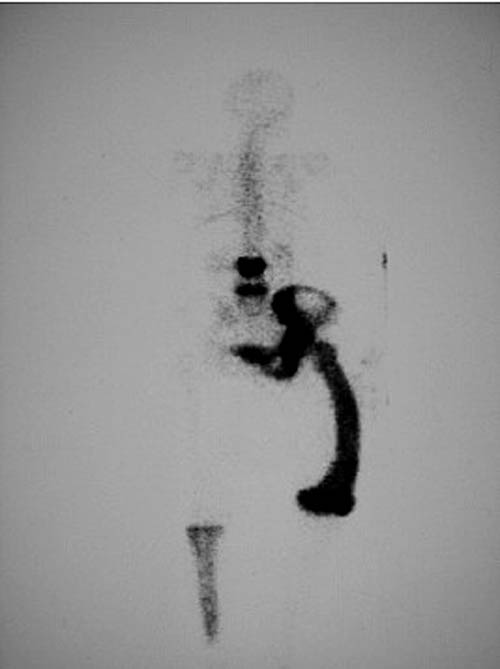

b. Scintigraphie

La scintigraphie osseuse au 99mTc permet de faire une cartographie de la répartition des lésions pagétiques qui apparaissent sous la forme de foyers hyperfixants (figure 1.9).

Fig. 1.9. Maladie de Paget. Aspect scintigraphique. Hyperfixations de L3, L5, de l’hémibassin gauche, du fémur gauche et du tibia droit caractéristiques (hyperfixations intenses et diffuses des os, déformation du fémur)